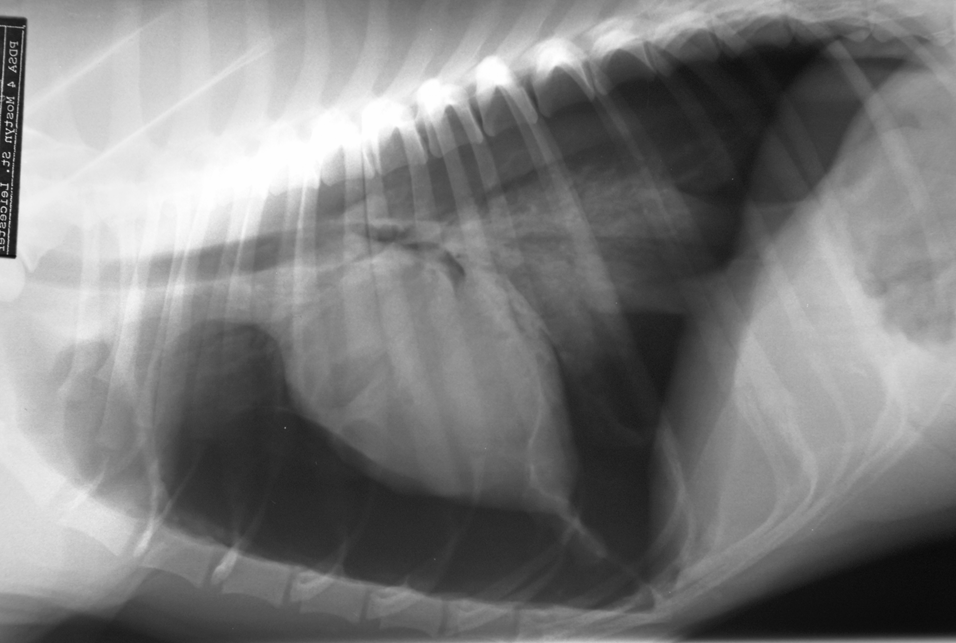

• what is the diagnosis?

diaphragmatic hernia

• which lung patterns can be seen?

alveolar and interstitial